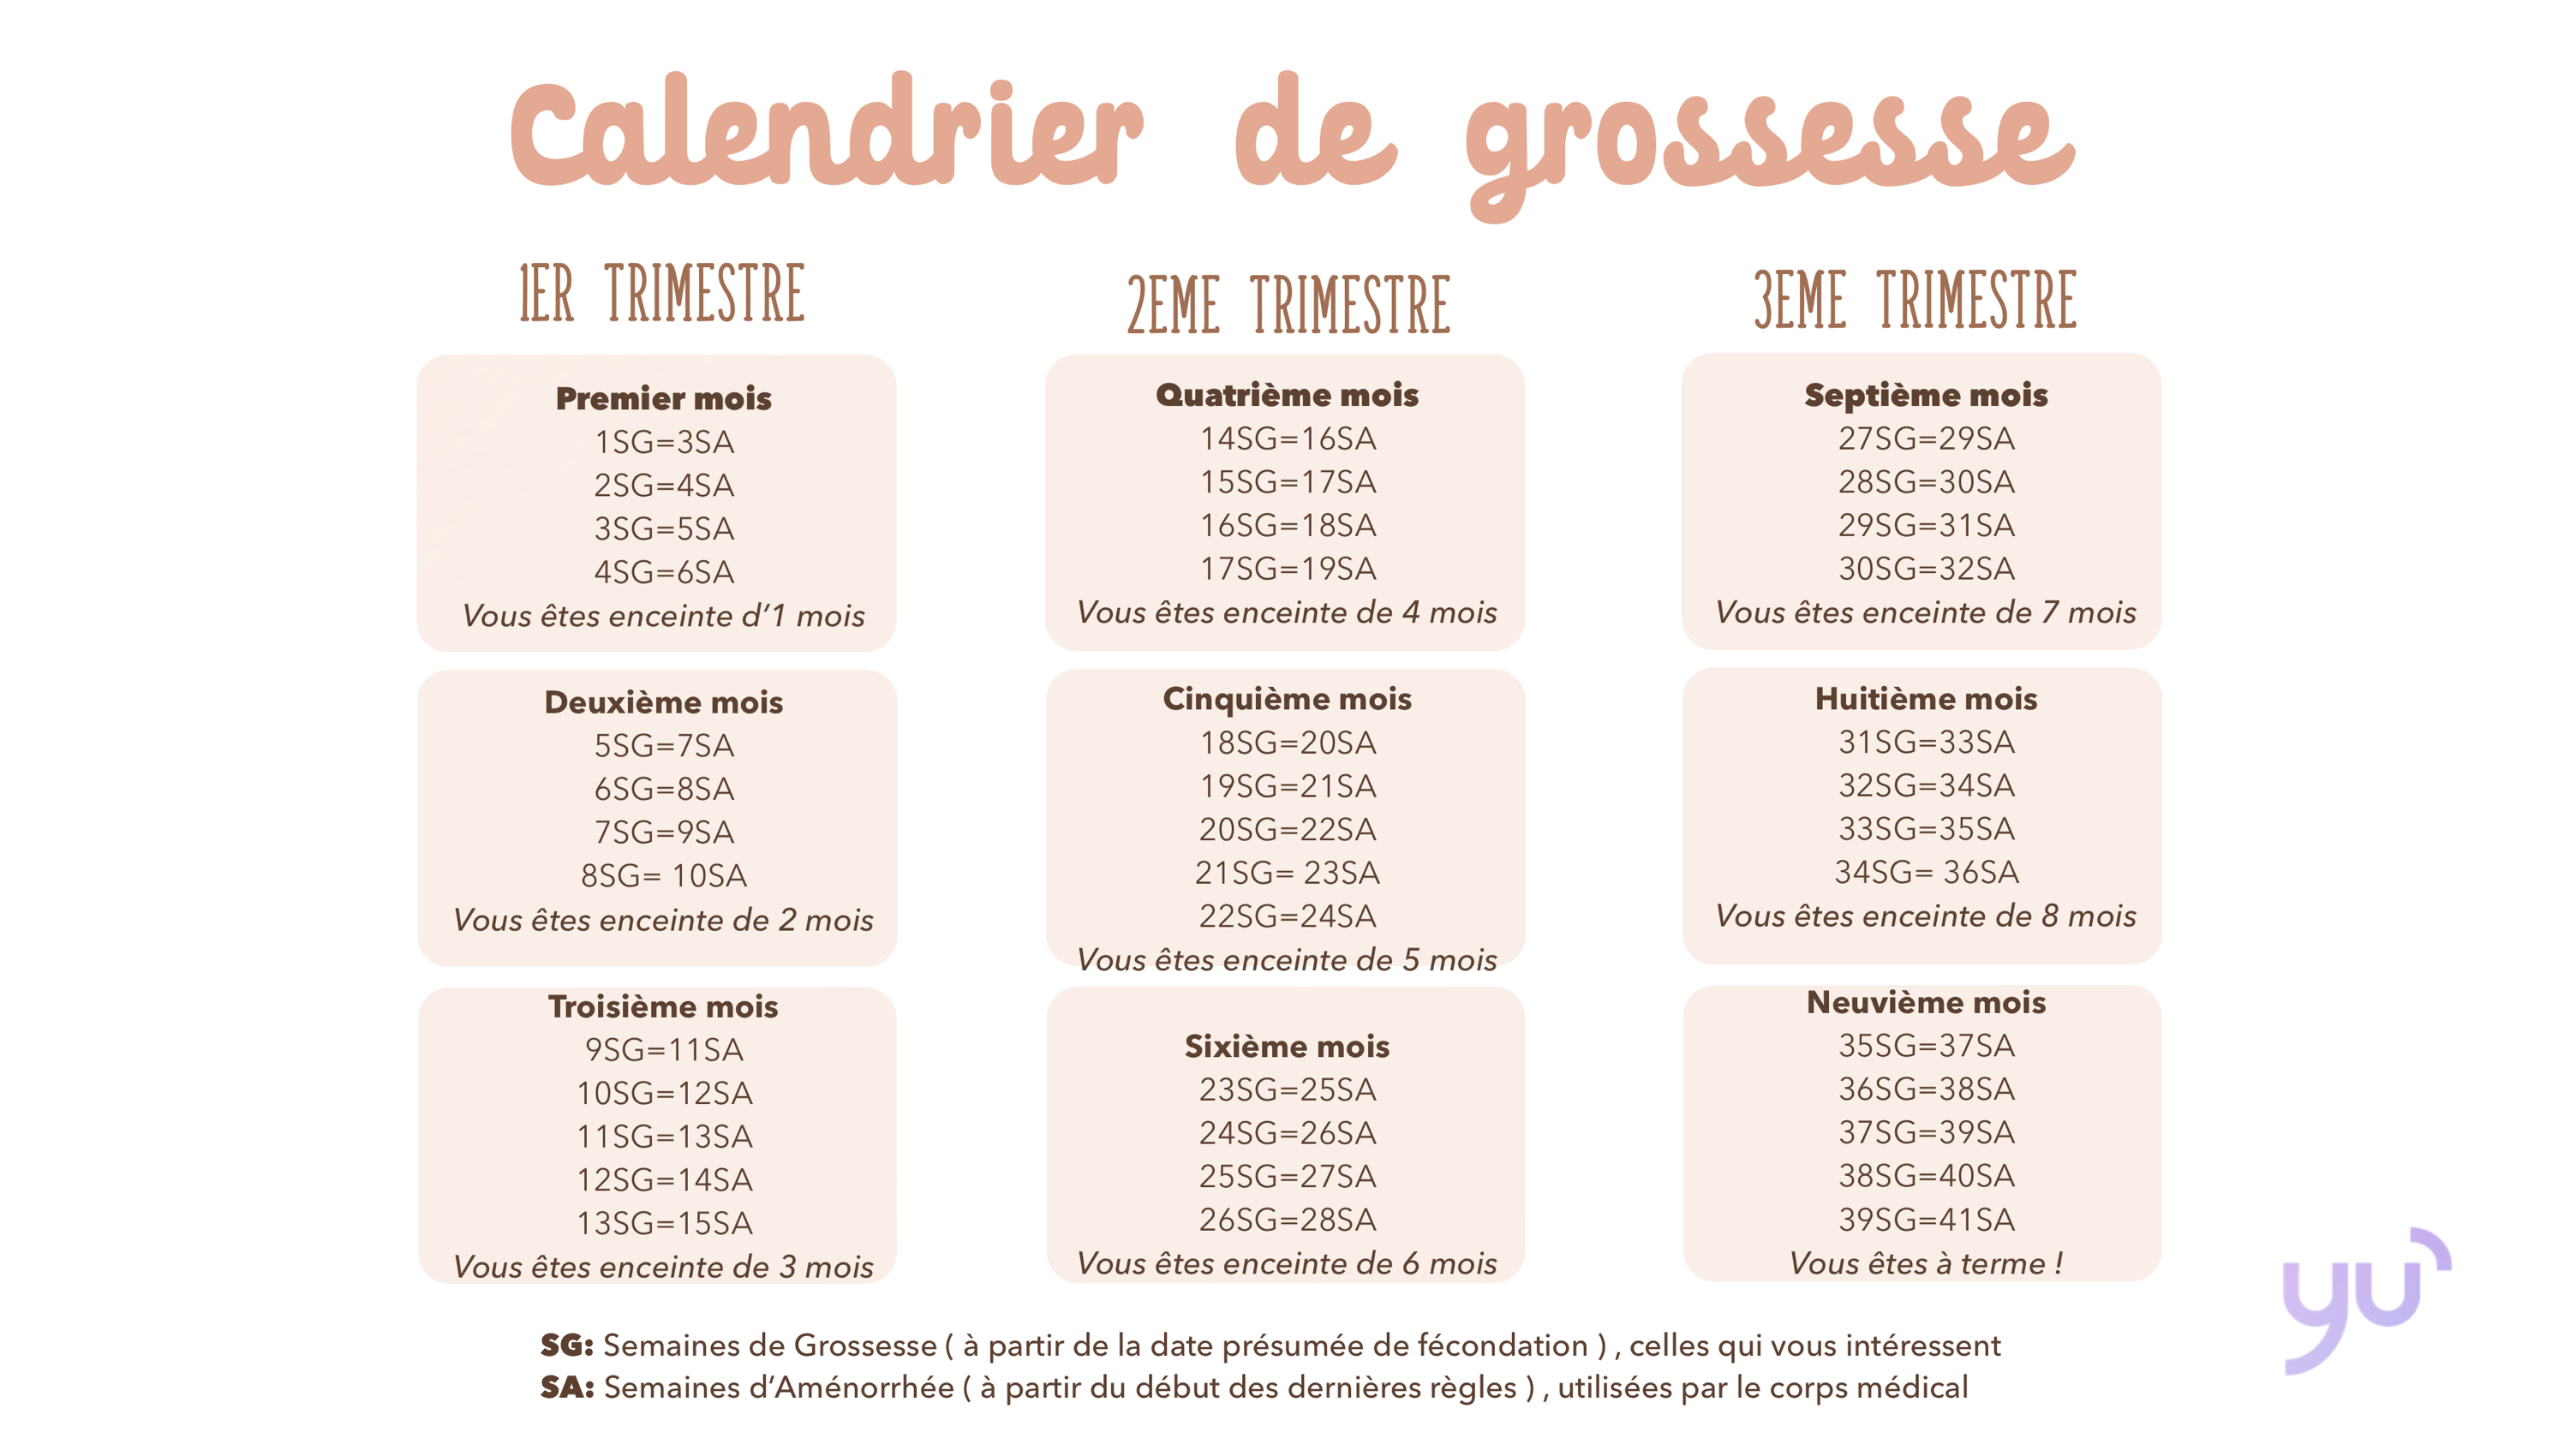

Comment les médecins calculent les semaines de grossesse ?

Comprendre comment les semaines de grossesse sont calculées est essentiel pour suivre le développement fœtal et préparer l’arrivée du nouveau-né. Les médecins utilisent une méthode standardisée pour déterminer l’âge gestationnel, crucial pour la surveillance médicale tout au long de la grossesse. Méthode de calcul standard Basée sur le dernier cycle menstruel La méthode la plus…